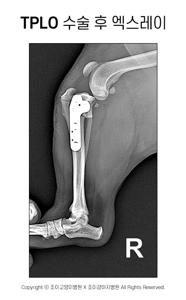

치료 방법

| 약물치료/보존적 치료 | 부분 파열, 소형견, 활동량이 적은 경우에 진통제, 운동 제한, 체중 관리 등 비수술적 치료 시도 가능 |

| 수술적 치료 | 완전 파열, 대형견, 활동량이 많은 경우, 보존적 치료에 효과 없을 때 필요. 대표적 수술로 TPLO, TTA, 인공 인대 대체 등이 있음 |

- 수술 후에는 입원, 재활치료, 체중 관리가 중요합니다.